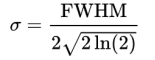

对图像进行空间滤波时,我们经常使用高斯核(Gaussian kernel),该平滑核的尺寸(平滑范围)由半高宽(full width at half maximum, FWHM)决定。如下图 3所示,半高宽是指:分布函数在其峰值一半位置上的峰宽。对于高斯分布而言,其半高宽与标准差存在关系:

图3半高宽

图3半高宽